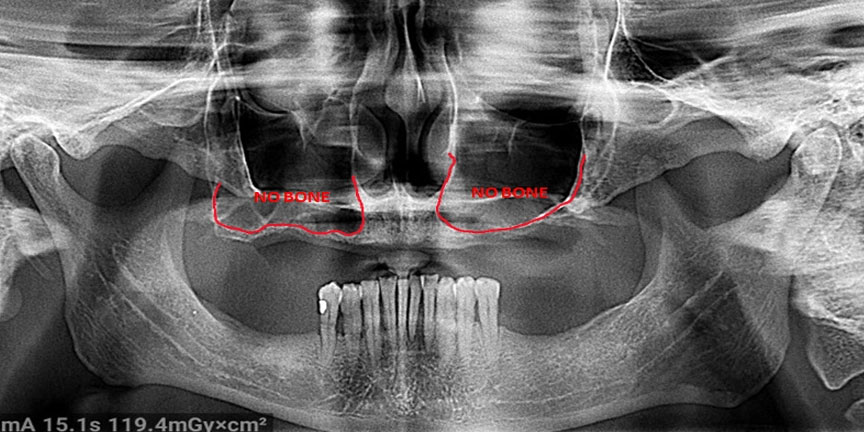

Severe Bone Loss

Difficult Cases

We treat patients when other providers cannot manage. CLICK HERE